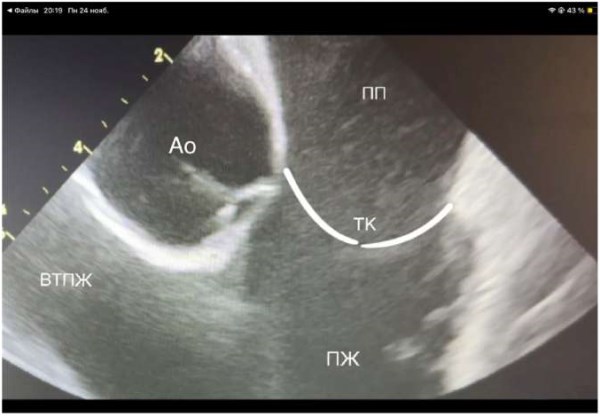

После проведения датчика в правое предсердие (ПП) его ось ориентируется на 12 ч (нос пациента в положении на спине без поворота головы), что отражается УЗ «домашней позицией», ориентиры ПП, трикуспидальный клапан, правый желудочек, корень аорты (рис. 2). Для безопасного позиционирования проводника транссептального интродьюсера необходимо визуализировать ВПВ. Следующее движение УЗ датчика — поворот по часовой стрелке на 3 ч. Анатомические ориентиры: ПП, левое предсердие (ЛП), межпредсердная перегородка, корень аорты, из этой позиции визуализируется ушко ЛП (рис. 3), при отсутствии признаков тромбоза принимается окончательное решение о проведении процедуры в ЛП. Для выведения ВПВ с помощью верхнего и нижнего колец управления луч датчика поворачивается кзади и вправо на 45°. Анатомические ориентиры: ВПВ, восходящая аорта, ЛП. Проводник через НПВ, ПП заводится в ВПВ под УЗ контролем и далее по нему транссептальный интродьюсер (рис. 4). После замены проводника на транссептальную иглу управляющие кольца УЗ датчика возвращаются в нейтральную позицию для визуализации межпредсердной перегородки, интродьюсер с иглой смещается вниз на овальную ямку. При затруднении пункции телом иглы возможна пункция внутренним стилетом с дальнейшим поэтапным проведением иглы на стилет, дилататора на иглу, интродьюсера на дилататор (рис. 5). По проведенному через интродьюсер в левую верхнюю ЛВ жёсткому проводнику проводится смена интродьюсера на доставляющее устройство для криобаллона. Выведенный за пределы доставляющего устройства баллон и циркулярный катетер хорошо определяются визуально (рис. 5), также показателем выведения баллона является метка на катетере. Управляя УЗ катетером вращением по и против часовой стрелки, а также с помощью управляющих колец изгибая катетер вперёд-назад и вправо-влево выводятся поочерёдно (по часовой стрелке) левые ЛВ, далее правая нижняя и правая верхняя ЛВ (рис. 6, 7). Стимуляционный катетер проводится в правый желудочек из «домашней позиции», а ВПВ по описанной ранее методике. Контроль окклюзии УЛВ осуществляется с помощью цветной допплероскопии (рис. 8, 9) и «пузырьковой пробы», для чего в просвет криобаллонного катетера вводится физиологический раствор. Контроль полости перикарда проводится из ПП (поворот из «домашней позиции» против часовой стрелки) и из правого желудочка (загибание управляющим кольцом кпереди), эту манипуляцию мы проводим как во время процедуры, так и перед завершением и извлечением УЗ катетера.

Рис. 2. «Домашняя позиция». Белым контуром выделены створки трикуспидального клапана и границы правого желудочка.

Сокращения: Ао — корень аорты, ВТПЖ — выходной тракт правого желудочка, ПЖ — правый желудочек, ПП — правое предсердие, ТК — трикуспидальный клапан.